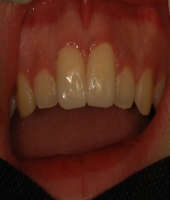

| ● 진료과목 : [심미보철] 돌출치아의 치료

| ● 내용 : 사고로 인한 돌출치아의 치료 |